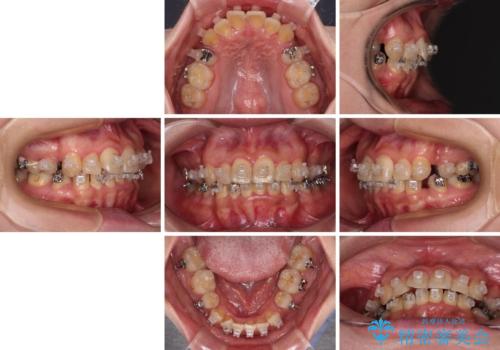

- 海外で抜歯矯正を開始し、治療途中で帰国したため、転院先を探しているとのことで来院された患者様です。

ワイヤーは抜けてしまい、後戻りが始まっている状態でしたが、既存の装置を継続利用して受け入れてくれる医院が見つからないとのことでした。

当院では、張り替える必要のある部位は張り替えることで継続することとし、抜歯スペースを閉じていくように治療を行うこととしました。

後戻りにリカバリーに少し時間を要しましたが、1年強の期間で無事に治療を終えることができました。